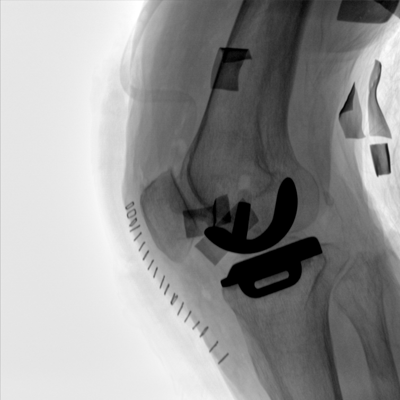

大尺寸動態平板探測器,高DQE、低噪聲、圖像清晰。采用多分辨率圖像增強處理技術,不同部位不同圖像處理算法,滿足客戶多樣化的需求。

采用智能變頻脈沖透視技術,優化圖像質量的同時降低輻射劑量,呵護醫患健康